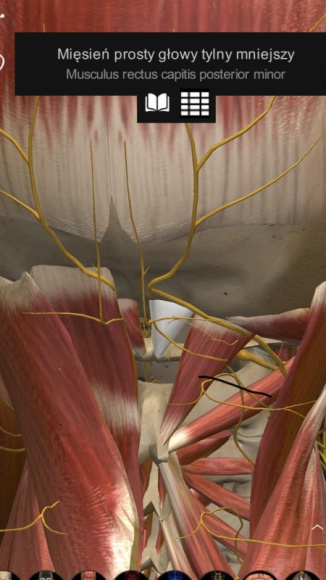

Charakterystyczne jest to, że w trakcie występowania bólu napinają się najczęściej mięśnie podpotyliczne.